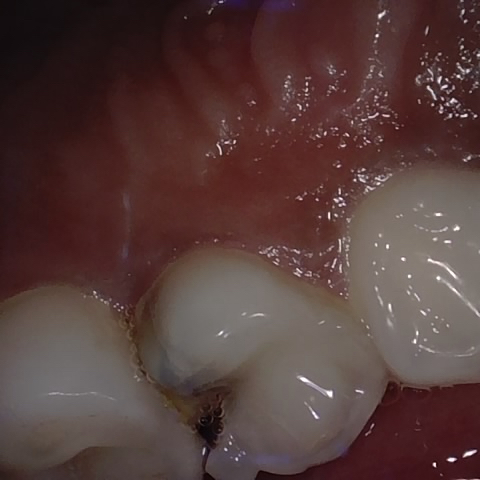

NHD39174

Annotated as "Good"